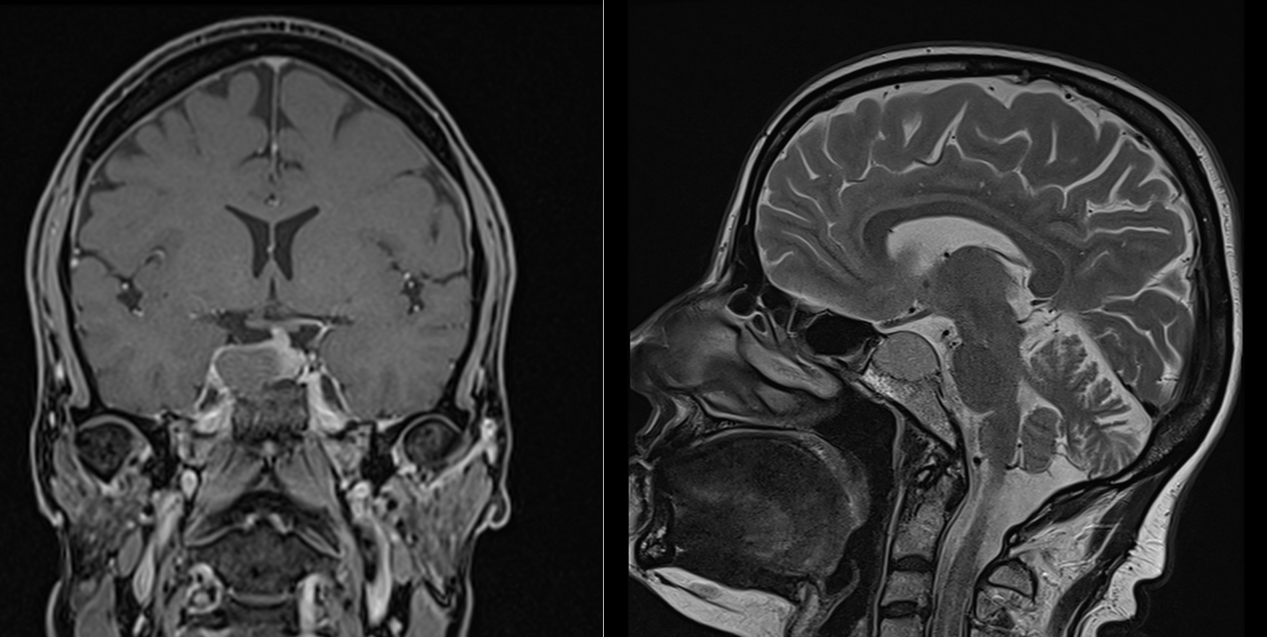

- RMN cerebral cu contrast este metoda de elecție pentru vizualizarea tumorii.

- Macroadenoamele hipofizare apar ca mase tumorale cu priza de contrast localizate la nivelul șeii turcești, eventual cu extensie superioară (supraselară) spre nervii optici sau, mai rar, inferioară, în sinusul sfenoid; de multe ori ele se pot extinde și lateral, în sinusurile cavernoase (structuri vasculare venoase formate în grosimea meningelui care mărginește lateral șaua turcească, prin care trec arterele carotide interne).

- Microadenoamele necesită un tip special de examinare RMN, cu secvențe repetate (în dinamică) realizate după administrarea substanței de contrast. Ele apar de obicei ca niște defecte de umplere – mici zone ne-gadolinofile (glanda hipofiză normală capteaza contrast mai repede decât adenomul); alteori singurul indiciu despre existența și localizarea adenomului (în afară de analizele hormonale) îl constituie asimetria glandei cu devierea tijei hipofizre de partea opusă